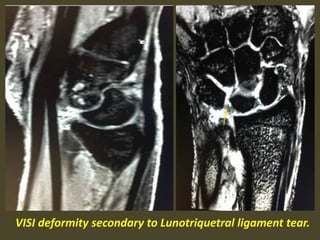

A simple approach is to consider the lunate

which is usually the easiest carpal bone to

visualize on a lateral wrist image. If the

lunate is abnormally tilted in a dorsal

direction on a standard lateral wrist image,

a DISI should be considered. If the lunate is

abnormally tilted in a volar direction a VISI

should be considered. DISI is due to

disruption of the scapho-lunate articulation.

VISI is secondary to disruption of the luno-

triquetral articulation.

VISI deformity secondary to Lunotriquetral ligament tear.